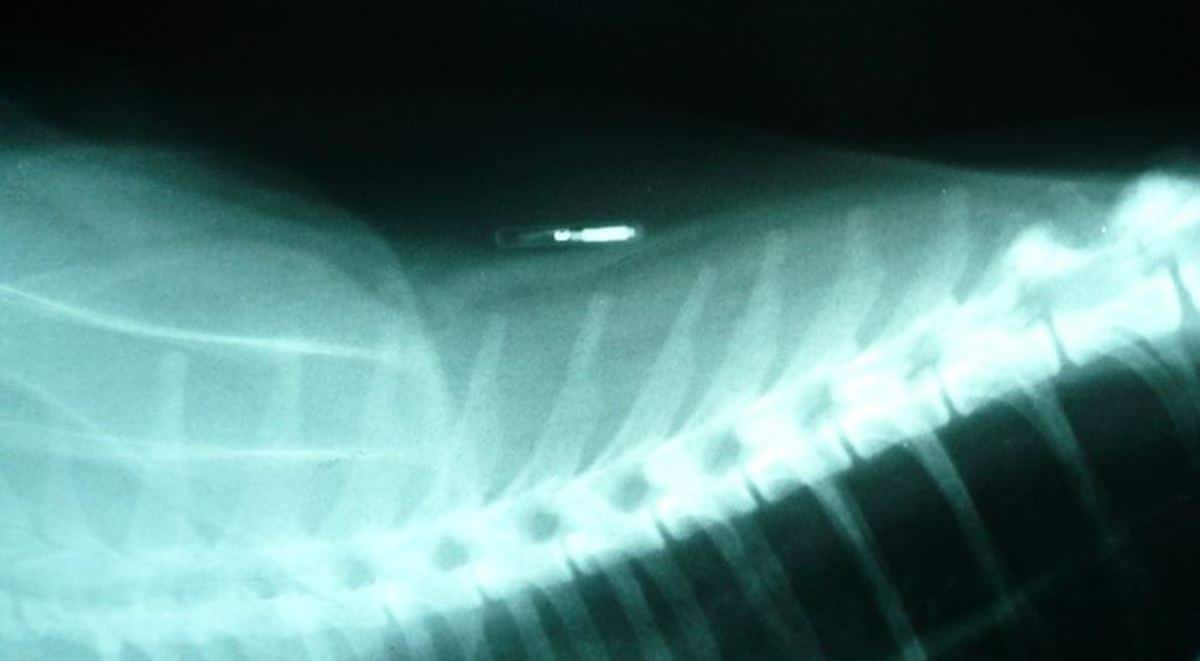

- RFID (Radio Frequency Identification)– In the form of a microchip that’s implanted under your pet’s skin and scanned to identify the pet as yours.

RFID’s eliminate the need to keep records on your pet’s health. If your pet gets lost and brought to a vet or shelter, their health information is available to the professionals handling them.